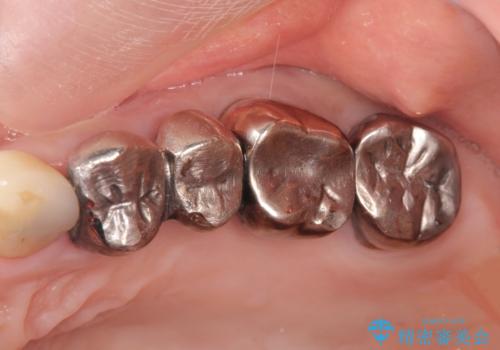

銀歯を外してのインプラント・セラミック治療

- 長年気になっている銀歯を外したい、と希望され来院されました。

銀歯を除去したところ大臼歯は十分な歯質が残っていたため残すことができましたが、小臼歯の2本は虫歯の再発により残っている歯質が非常に少なく破折リスクが非常に高いと判断しました。